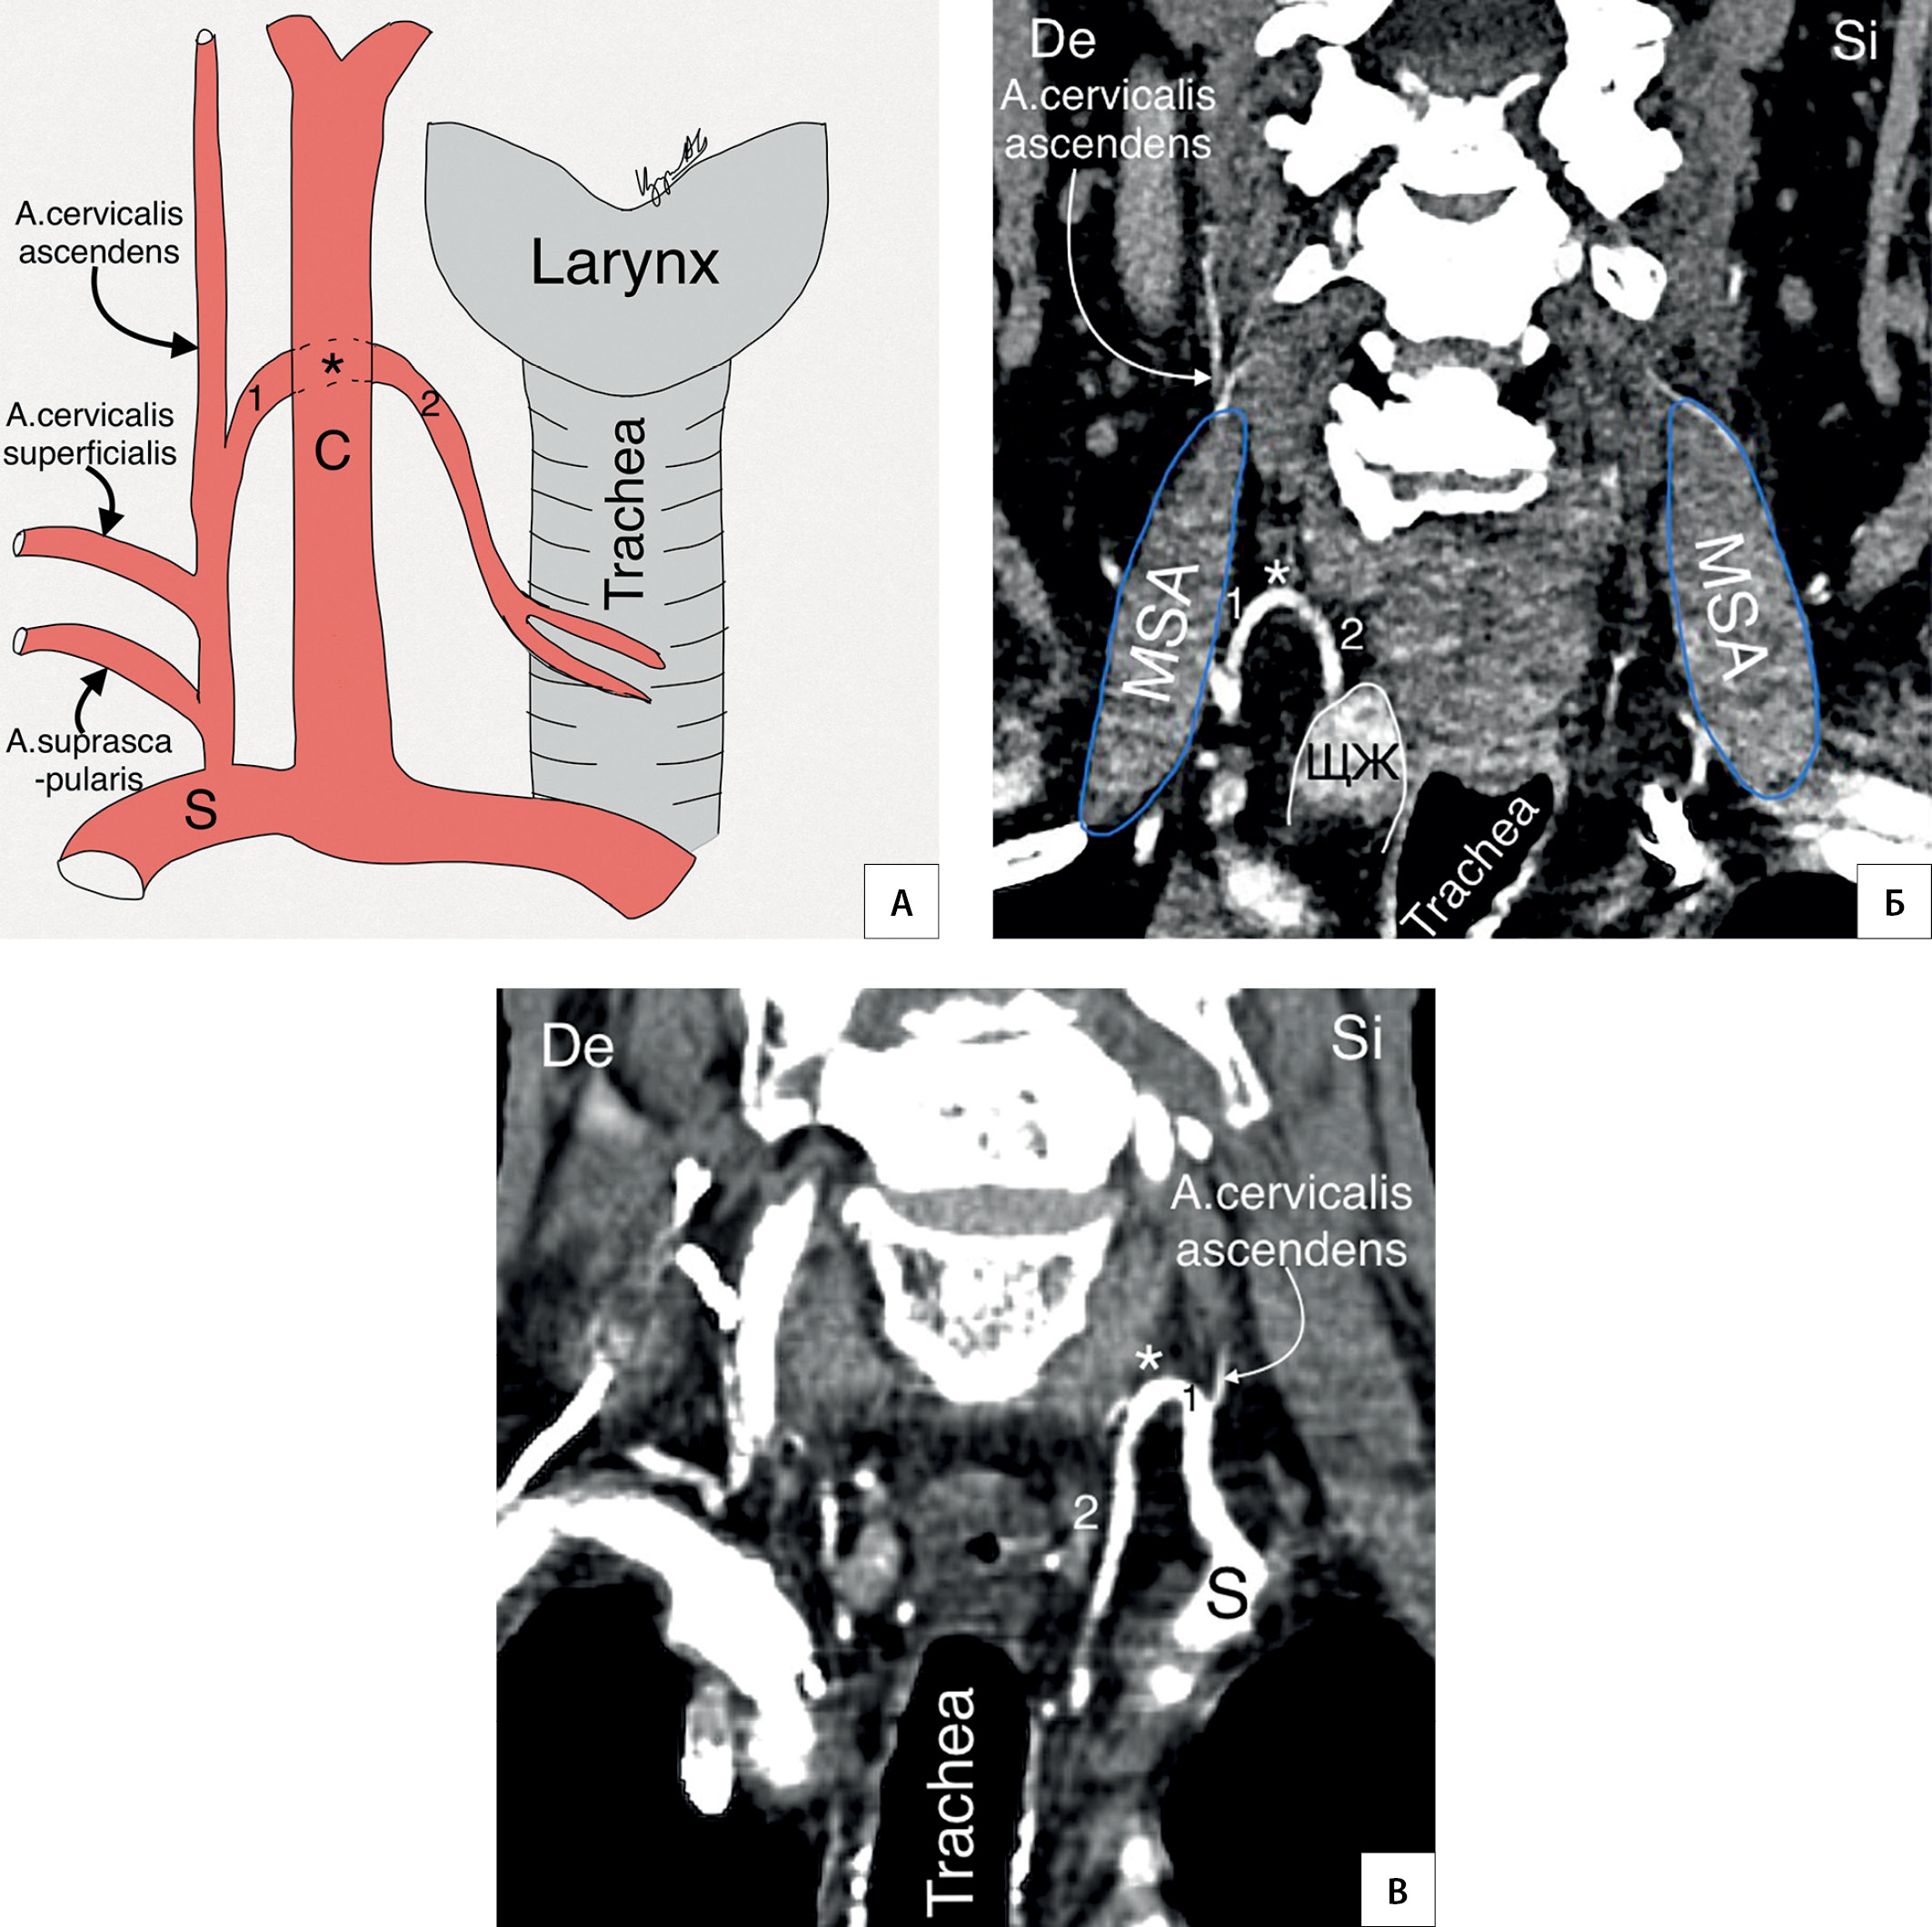

2. Рисунок 2. Топография НЩА. А — схематичный рисунок правого щитошейного ствола; Б — КТ-ангиография (фронтальный срез). Правая НЩА; В — КТ-ангиография (фронтальный срез). Левая НЩА. 1 — восходящая часть НЩА; * — колено НЩА; 2 — нисходящая часть НЩА; S — a. subclavia; C — a. carotis communis; MSA — musculus scalenus anterior; De — dextra; Si — sinistra. | |